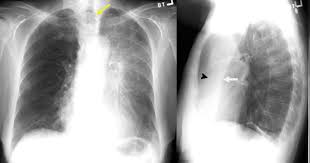

Retrocardiac air space disease. Airspace disease is considered chronic when it persists beyond 4-6 weeks after treatment. Tendency to coalesce near hila. The margins of airspace disease are fuzzy and indistinct.

Air-space opacification is a descriptive term that refers to filling of the lung parenchyma with material that attenuates x-rays more than the unaffected surrounding lung tissue. Consolidation or ground-glass opacity occurs when alveolar air is replaced by fluid pus blood cells or other material. Test results for infl uenza virus respiratory fl uorescent antibodies D3 Ultra DFA Respiratory Virus Screening and In-fectious Disease Kit.

Air cant get through the consolidation so your lung cant do its job of bringing in fresh air and removing the air your body has used. The location retrocardiac - behind the heart shouldnt make a difference. Identifying multifocal air-space disease on CXR can be a significant clue to COVID-19 pneumonia.

By early detection and proper evaluation of the abnormal retrocardiac shadows the radiologist may establish the diagnosis before the clinical signs and symptoms of compression of large blood vessels and nerves become. Retrocardiac Air Space Disease. Air space opacification is a descriptive term that refers to filling of the pulmonary tree with material that attenuates x-rays more than the surrounding lung parenchyma.

This unusual type of bibasilar atelectasis happens when the lung is trapped as a result of pleural disease while being devoid of air. The opacities tend to be confluent merging into one another. These represent air-space or acinar nodules.

It is one of the many patterns of lung opacification and is equivalent to the pathological diagnosis of pulmonary consolidation. The latter will often reveal air trapping on expiratory images 25-27.

Airspace disease is considered chronic when it persists beyond 4-6 weeks after treatment. A single retrocardiac air-fluid level on a chest radiograph typically implies the presence of a sliding hiatal hernia. This unusual type of bibasilar atelectasis happens when the lung is trapped as a result of pleural disease while being devoid of air. Airspace disease also known as alveolar lung disease is a generic term thats used to describe abnormalities on chest x-ray or CT. The most common clinical causes of this CT pattern of disease include hypersensitivity pneumonitis sarcoidosis atypical infections eg those caused by Mycoplasma pneumoniae with associated bronchiolitis and acute interstitial pneumonia 25. The 2021 edition of ICD-10-CM J984 became effective on October 1 2020. J984 is a billablespecific ICD-10-CM code that can be used to indicate a diagnosis for reimbursement purposes. And retrocardiac air space disease. Retrocardiac Air Space Disease.

The location retrocardiac - behind the heart shouldnt make a difference. It is the radiological correlate of the pathological diagnosis of pulmonary consolidation. The most common clinical causes of this CT pattern of disease include hypersensitivity pneumonitis sarcoidosis atypical infections eg those caused by Mycoplasma pneumoniae with associated bronchiolitis and acute interstitial pneumonia 25. The particular way the lung collapses can often produce a. Acinar or air-space nodules. CT 5-mm slice thickness in a patient with bilateral consolidation. Tendency to coalesce near hila.